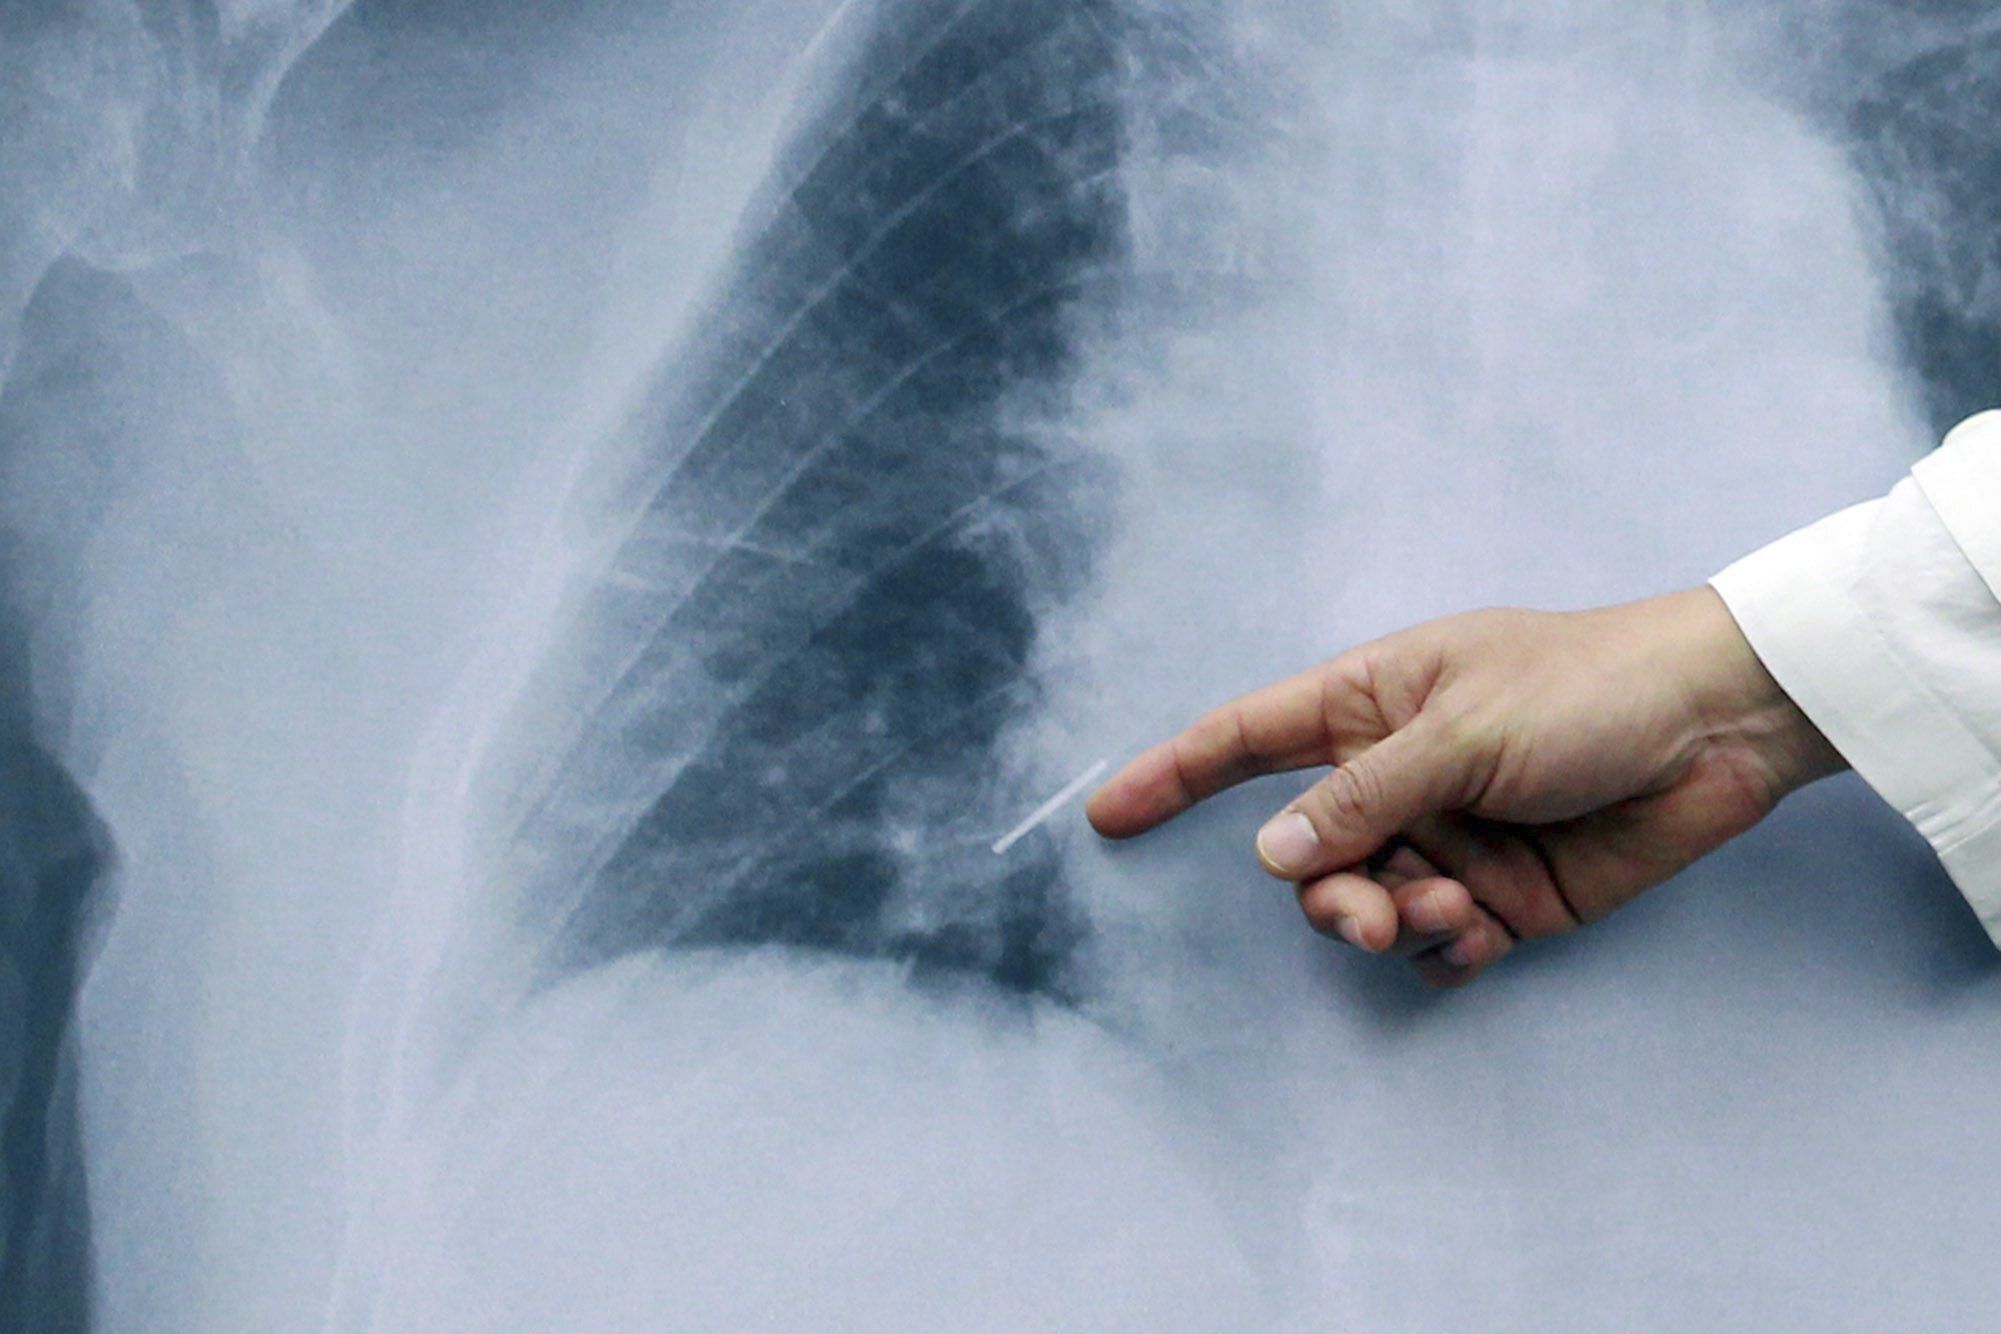

Pulmones

El médico puede recomendar radiografías para ayudar a controlar el avance de la artritis reumatoide en las articulaciones con el tiempo. Las pruebas por resonancia magnética y ecografía pueden ayudar al médico a determinar la gravedad de la enfermedad en el cuerpo.